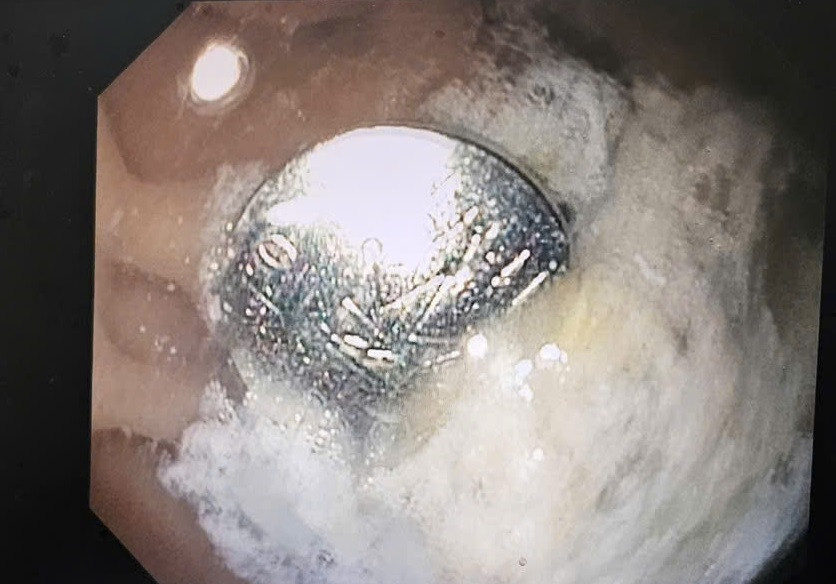

| Cục pin được phát hiện nằm trong dạ dày của bệnh nhi trên hình ảnh nội soi |

Phát hiện sự việc, gia đình đã vội đưa bé đến bệnh viện cấp cứu. Sau khi tiếp nhận, bác sĩ nhanh chóng chỉ định chụp X-quang ổ bụng và phát hiện cục pin đang nằm trong dạ dày.

Sau hội chẩn khẩn, các bác sĩ thống nhất chỉ định nội soi can thiệp, gắp thành công cục pin ra khỏi đường tiêu hóa cho bệnh nhi.